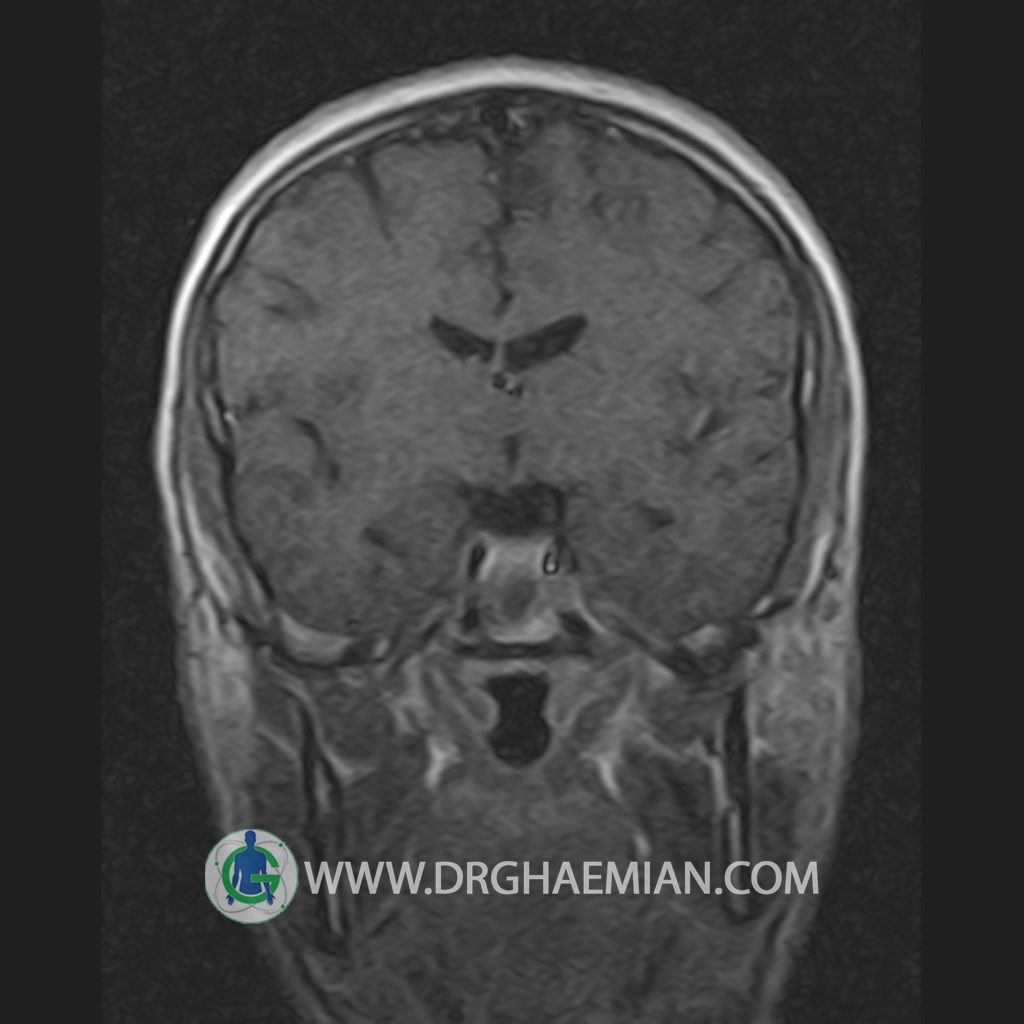

پزشکان اغلب از تصویربرداری ام آر آی برای تشخیص و درمان عارضه های پزشکی که فقط با استفاده از اشعه ایکس یا میدان مغناطیسی و امواج رادیویی قابل مشاهده است، استفاده می کنند. دستگاه ام آر آی تصاویر دقیق از ساختار های داخلی بدن ایجاد می کند. در این کیس یک میکروآدنوم در هیپوفیز بیمار مشاهده می شود.

HYPOPHYSIS MRI

(with and without contrast)

Technique: Axial , coronal T1 , Axial , coronal , sagittal T2 , Axial, coronal T1 post Gd & 64 dynamic thin coronal slices.

The infundibulum is centered and of normal size .

The optic chiasm and suprasellar spaces appear normal .

The cavernous sinus and imaged portions of the internal carotid artery and carotid siphon are unremarkable .

Evaluable portions of the neurocranium show no abnormalities .

The sphenoid sinus is clear and pneumatized .

Imaging of the hypothalamus after contrast medium administration was normal.

– Small hypoenhancing mass lesion ( 3 x 4 mm ) in posterior of pituitary stalk suggestive for micro adenoma

– Mucosal thickening in ethmoid & maxillary sinuses

is seen